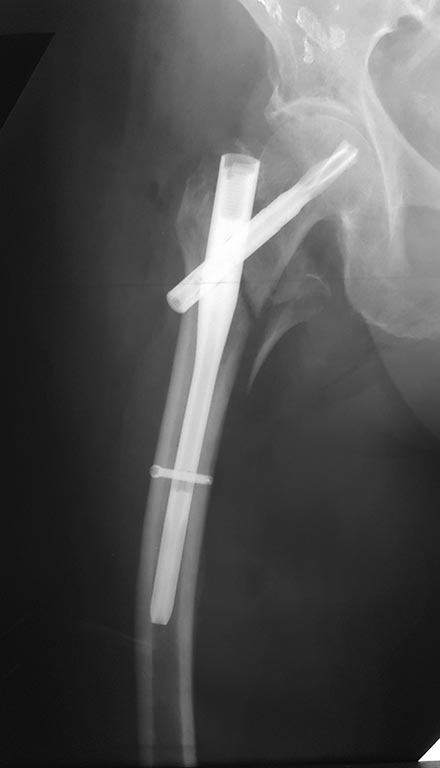

Уважаемые коллеги! Пациентке 86 лет. Чрезвертельный перелом фиксирован

PFNa. На послеоперационной рентгенограмме выявлена выраженная варусная

деформация бедра, компенсаторная перестройка кости на вершине

деформации. Возможно ли развитие ползучего перелома на уровне конца

стержня и, если да, как предотвратить это?